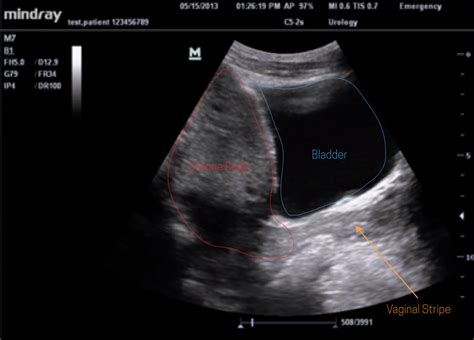

• posterior cul de sac ultrasound

• posterior cul de sac fluid

• posterior cul de sac radiology